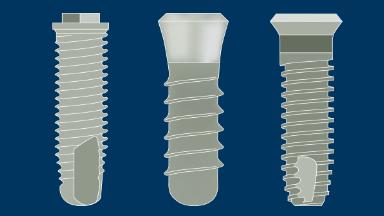

Desde a introdução dos implantes dentários, a pesquisa demonstrou que a eficácia clínica das próteses implantossuportadas é igual ou superior ao desempenho da terapia protética convencional fixa ou removível. O sucesso cientificamente documentado dos implantes levou ao desenvolvimento de muitos desenhos diferentes de implantes, materiais, tecnologias de superfície e métodos cirúrgicos. Numerosas empresas fabricam e comercializam sistemas de implantes, e a maioria desses sistemas inclui implantes de mais de um desenho. Atualmente, existem mais de 2.000 desenhos de implantes disponíveis em todo o mundo. Além disso, alguns desses sistemas incluem componentes protéticos projetados para serem compatíveis apenas com implantes do mesmo fabricante. Portanto, a escolha de um sistema de implante requer uma consideração cuidadosa. Este módulo irá rever os vários fatores que influenciam o clínico a selecionar o sistema mais adequado para seus pacientes.

- descrever as características do produto que influenciam a seleção do sistema